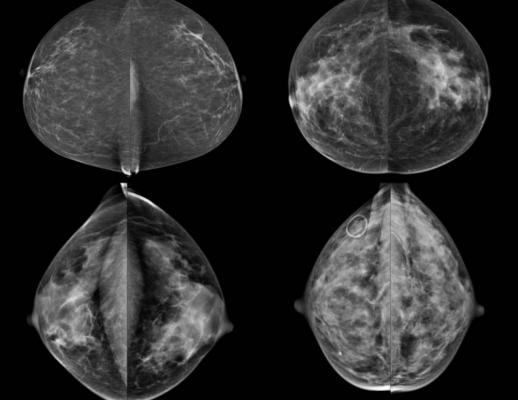

Breast density has been categorized through the Breast Imaging Reporting and Data System (BI-RADS). Breasts are defined as: a) mostly fatty, b) scattered density, c) consistent density and d) extremely dense. Higher breast density modestly increases a woman’s risk of developing breast cancer and decreases the sensitivity and specificity of screening mammograms. Women classified with dense breasts (categories c and d) may be offered supplemental screening with ultrasound or magnetic resonance imaging (MRI). However, the study shows this approach may not be supported by strong scientific evidence.

The first problem is the inability to accurately assess whether a woman has dense breasts to begin with. One study showed that different radiologists assigned the same BI-RADS category to an individual woman only 82 percent of the time. Other data showed that as many as 22 percent of women were reclassified from dense to non-dense (on vice versa) on consecutive mammograms.